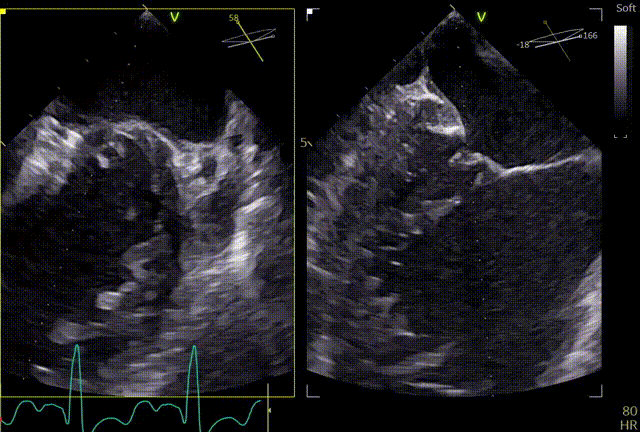

第一个夹子XTW

关小夹子,进入到左室后,跨瓣越过瓣叶尖端后,立马打开夹子,三维再次确认夹臂方向未改变,慢慢往上提拉,一次准确捕获瓣叶,前后叶Bouncing明显,后叶接近根部,关紧夹臂,反流量整体减少,但是内外侧都残余反流,内侧为主。反流明显减少,后叶夹持10mm以上,夹子稳定性良好,跨瓣压差小于3mmHg,决定释放。

释放前评估

释放后

释放后内侧后叶仍旧栓系,反流较重,内外侧都残余反流,内侧为主,考虑到内侧反流较宽,瓣叶够长,栓系难以捕捞,压差不高,第二枚夹子选择XTW,置入第二枚XTW后,在1区上方做轨迹测试,充分释放张力,调整夹子的夹臂方向位于5点-11点的位置,回拉系统,使第二枚夹子位于3区,关小夹子进入到心室侧,由于第一枚夹子起到了稳定瓣叶的作用,第二枚夹子捕捞夹持也异常顺利,一次精准捕获前叶和后叶,再次完整评估二尖瓣夹XTW的方向、组织桥稳定性、瓣叶受限程度及反流减小程度。前后叶Bouncing明显,但是反流却明显增加,开始未明确原因,Orientation,夹持量均无问题,但是内侧还残余反流,考虑内侧可能还要补,决定打开贴近第一个夹子放置,如果有需要内侧再补,此时发现由于患者EF值低,麻醉老师肾上腺素一直在给,心脏搏动较为剧烈,反流术中的异常增多可能是由于此原因导致,遂停止给药。

第二个XTW第一次夹持

第二个XTW第二次夹持